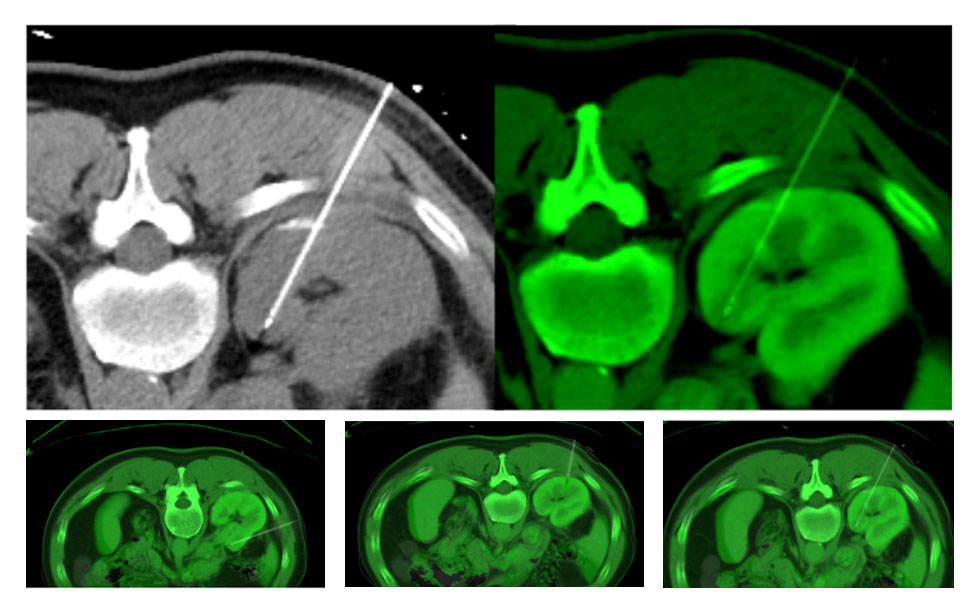

IGTFusion used to guide and confirm accurate needle placement in 3 renal lesions that were not visible on CT during the procedure.

- Registered a supine pre-procedural image to a prone procedural image